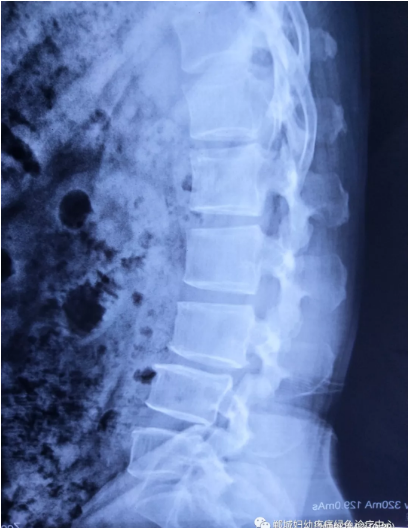

不經(jīng)意間聽到有人說醫(yī)院疼痛科可以不吃藥不打針,用無痛苦、無創(chuàng)傷的方法治療腰痛。陳女士就抱著試試看的心理來到了鄲城縣婦幼保健院疼痛科,疼痛科時慶祥主任詳細(xì)了解病情,結(jié)合腰椎磁共振及體征后告訴陳女士她不用手術(shù),通過腰椎脊柱定位周期減壓牽引系統(tǒng)(外星艙)也能解決腰痛、腰椎滑脫、腰椎反弓這些問題。陳女士未曾想到經(jīng)過十五天的治療后腰部及下肢放射性疼痛癥狀基本消失。陳女士感到十分激動與感謝,就在當(dāng)?shù)匦l(wèi)生院做了一個腰椎正側(cè)位x片和之前的片子作對比,發(fā)現(xiàn)腰椎滑脫明顯改善。她說道:感謝鄲城縣婦幼保健院疼痛科的所有醫(yī)護(hù)人員、感謝外星艙脊柱減壓治好了我的腰痛,也感謝告訴我來這里的人,她的一句話,讓我省了好幾萬元的手術(shù)費!

治療后